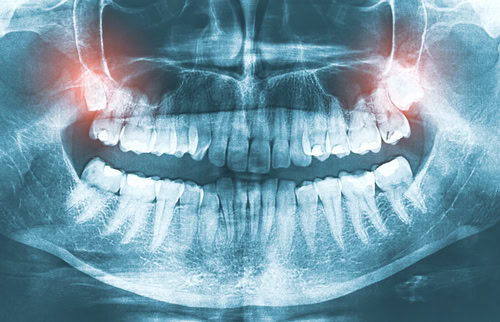

Digital radiography integrates computer systems and digital sensors to capture, display, store, and distribute radiographic visuals. This modern approach presents a clear edge over its traditional film-based counterpart. A primary advantage is the considerable reduction in radiation exposure for patients.

Instead of using film, an electronic pad or sensor captures the digital image. Once captured, the image is directly saved to the patient’s digital record. From there, it’s readily available for on-screen viewing, distribution, or printing.